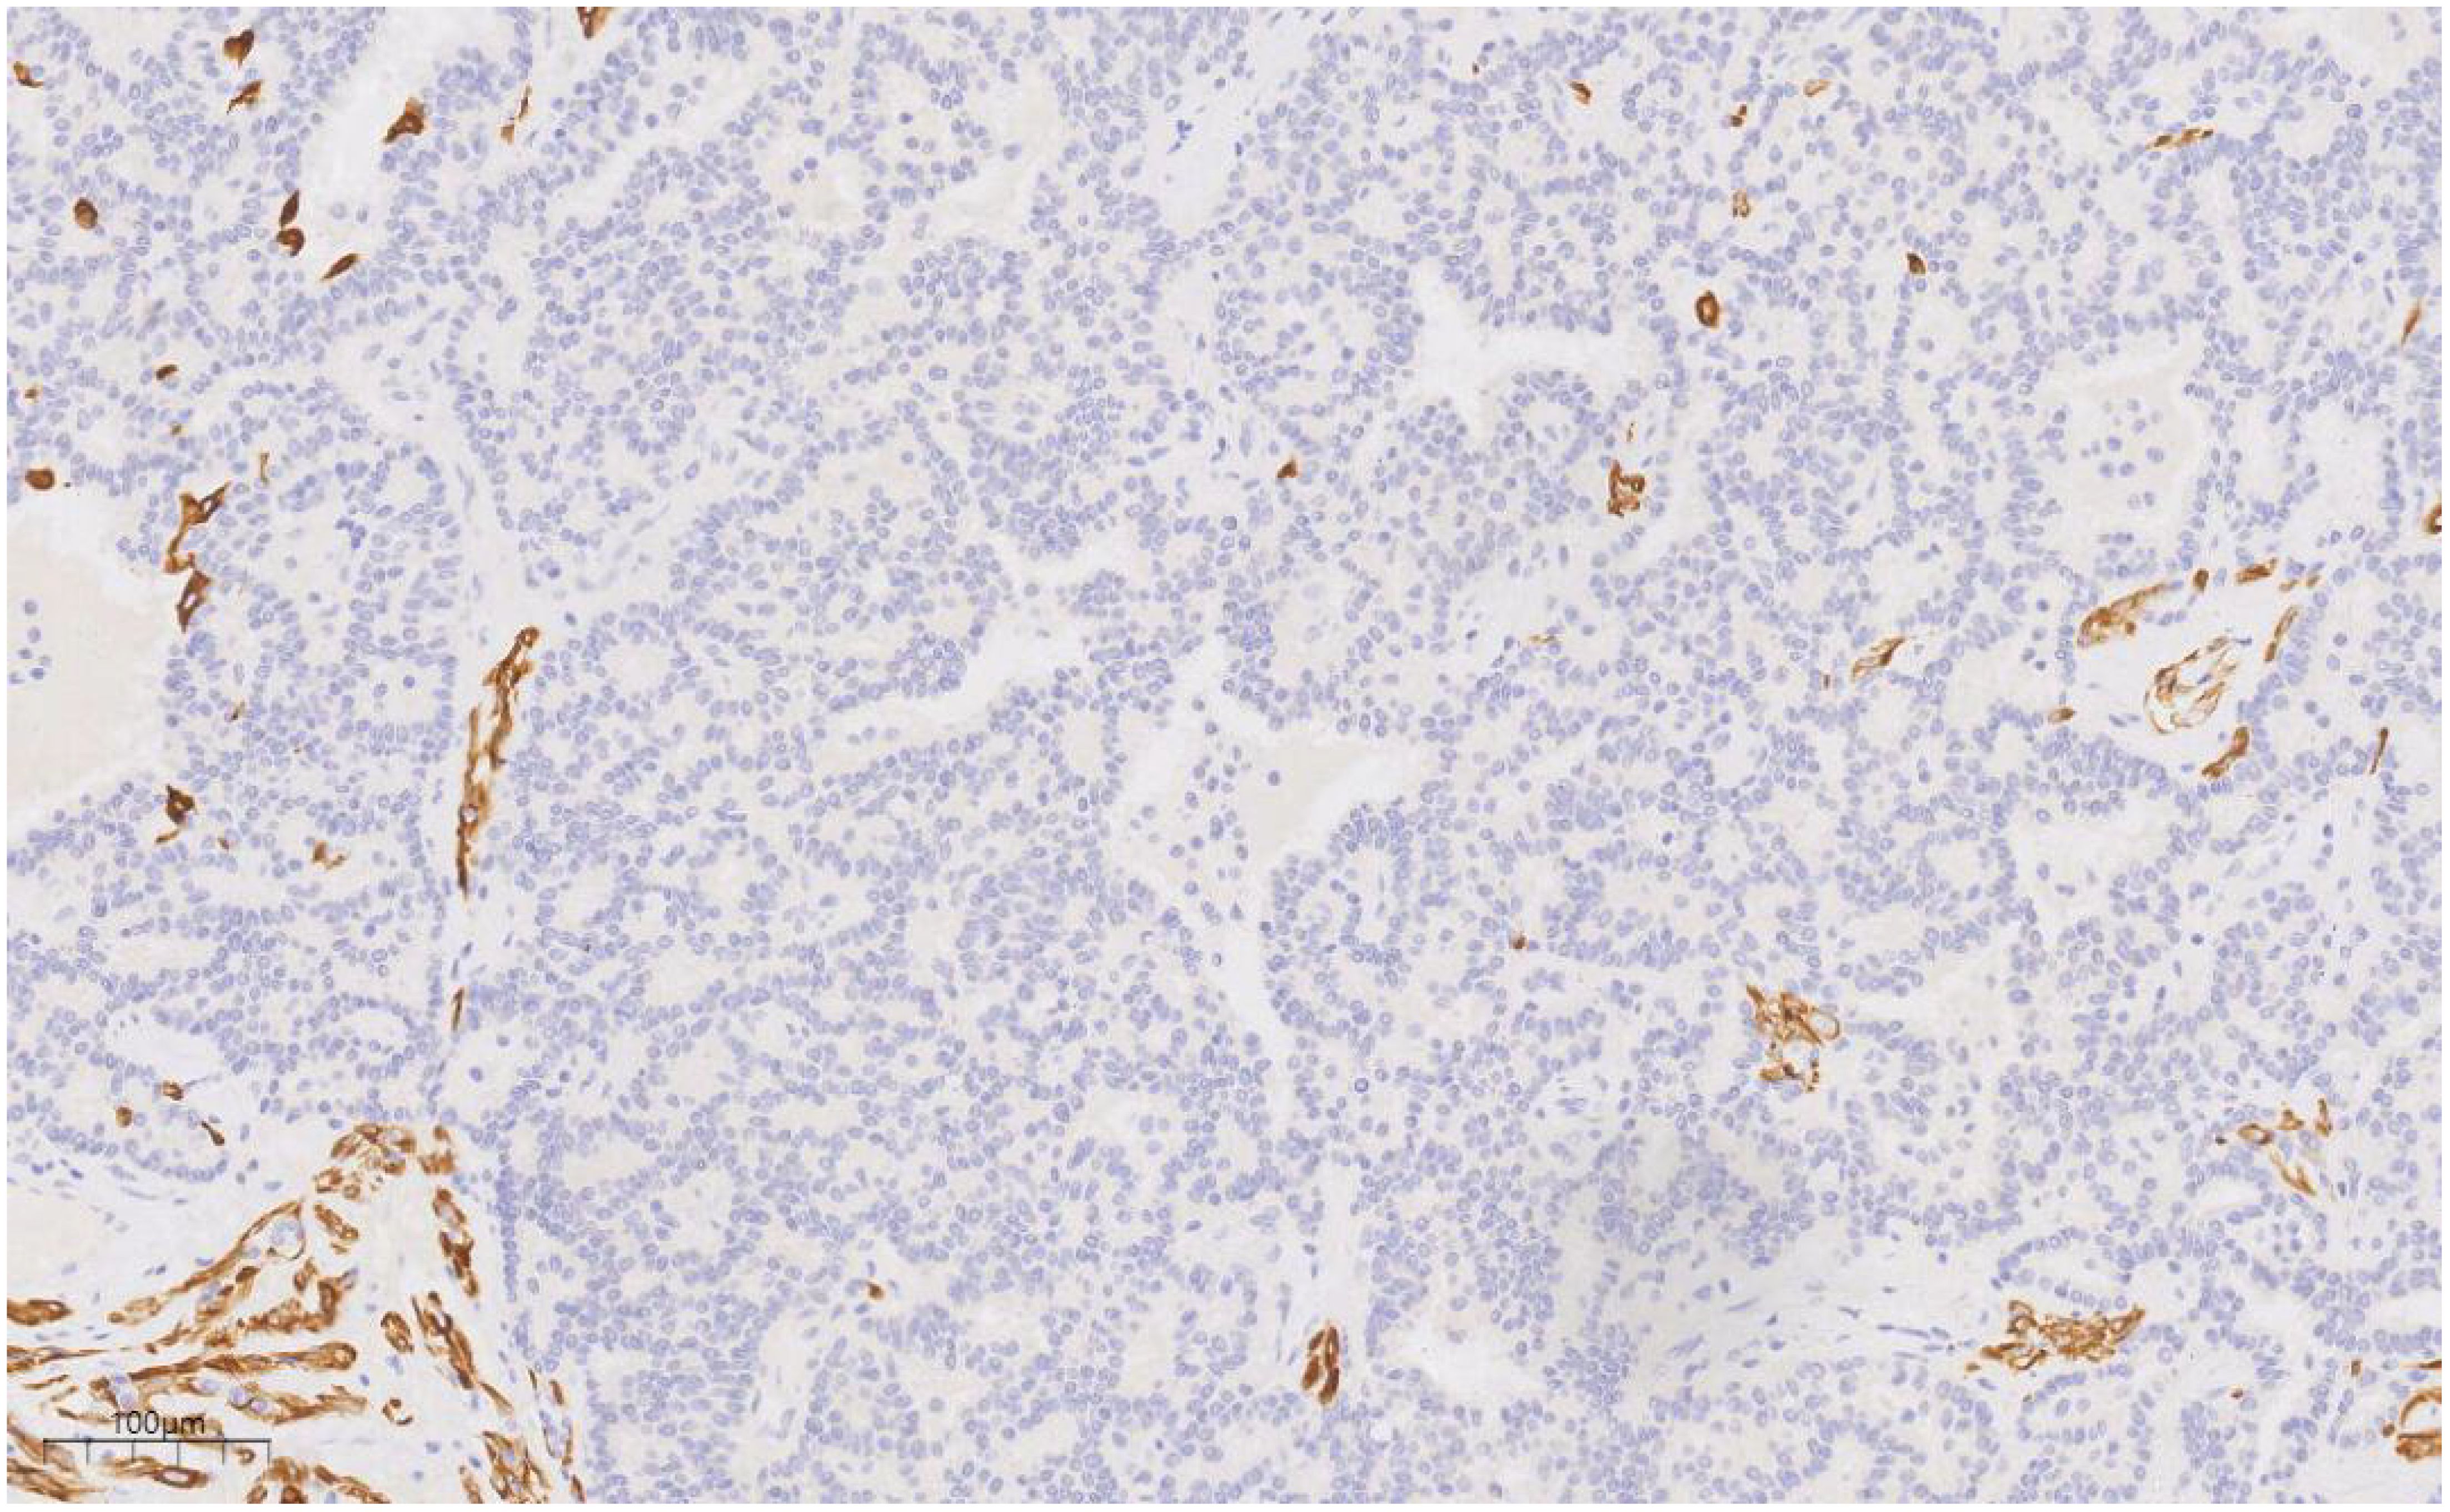

Figure 6

Microscopic view of tissue showing numerous small, purple-stained cells scattered throughout. There are brown areas outlined irregularly, possibly indicating stained structures. The scale in the bottom left corner measures one hundred micrometers.

Figure 6. CK5/6 labeling results suggest the presence of myoepithelial cells around the duct, and the absence of myoepithelial cells in some areas of the proliferative duct epithelium. EnVision, ×100.

Immunophenotype

Immunohistochemistry is essential for the characterization of papillary lesions. In this case, myoepithelial markers, including p63 and basal cytokeratins (CK5/6), were consistently expressed along the majority of the papillary axes and ductal periphery, confirming the presence of an intact myoepithelial layer surrounding the papillary structure. In contrast, the epithelial component within the DCIS foci exhibited a uniform, monoclonal profile: tumor cells demonstrated strong and diffuse ER positivity, coupled with the complete absence of high molecular weight keratins (e.g., CK5/6). Immunohistochemistry also plays a crucial role in assessing invasion and refining the differential diagnosis. The loss of myoepithelial marker expression (e.g., p63, SMMHC) in the fibrovascular core or periphery of the lesion generally suggests papillary carcinoma over benign papilloma (9, 10). In this case, although focal attenuation of myoepithelial staining was observed within portions of the papillary axis, a continuous p63-positive myoepithelial layer encircled the ducts, supporting an in situ process. The immunophenotypic findings, in combination with the morphological features, confirm a predominantly benign papilloma with focal low-grade DCIS.